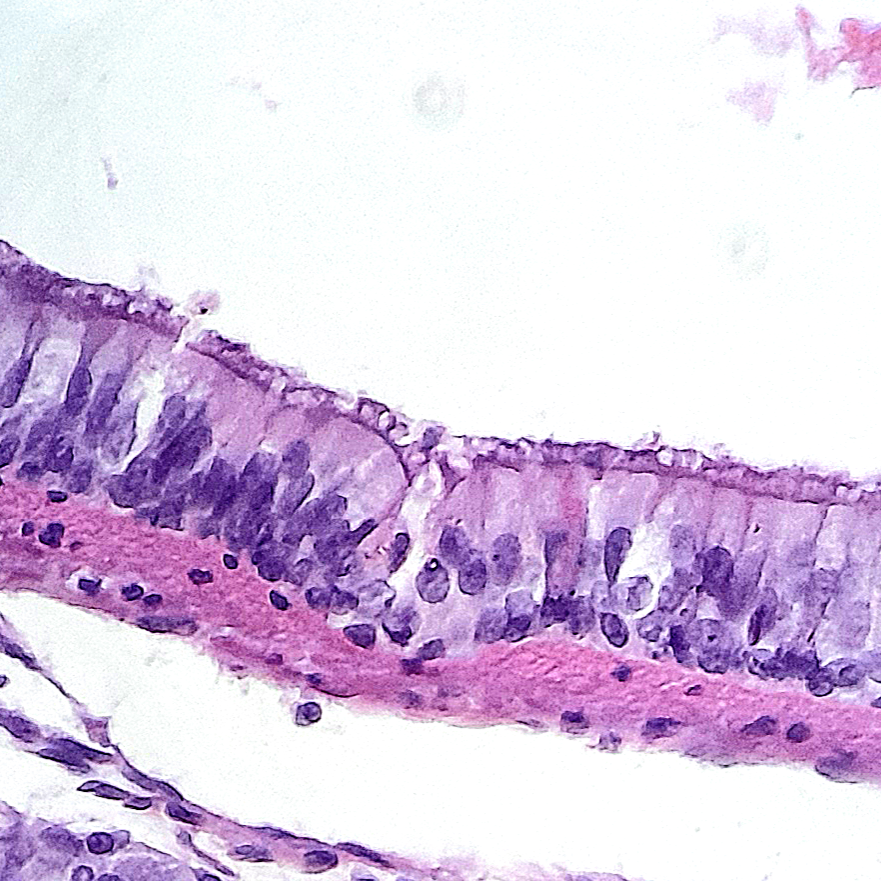

Sistema Respiratório

O sistema respiratório é responsável pela troca gasosa entre o organismo e o ambiente, permitindo a entrada de oxigênio e a eliminação de dióxido de carbono. Ele é composto por várias estruturas, incluindo; vias aéreas superiores (nariz, faringe e laringe), e vias aéreas inferiores (traqueia, brônquios e pulmões) e os músculos respiratórios, como o diafragma e os intercostais. O tecido é composto pelo epitélio pseudoestratificado ciliado, apresentando também glândulas caliciformes.